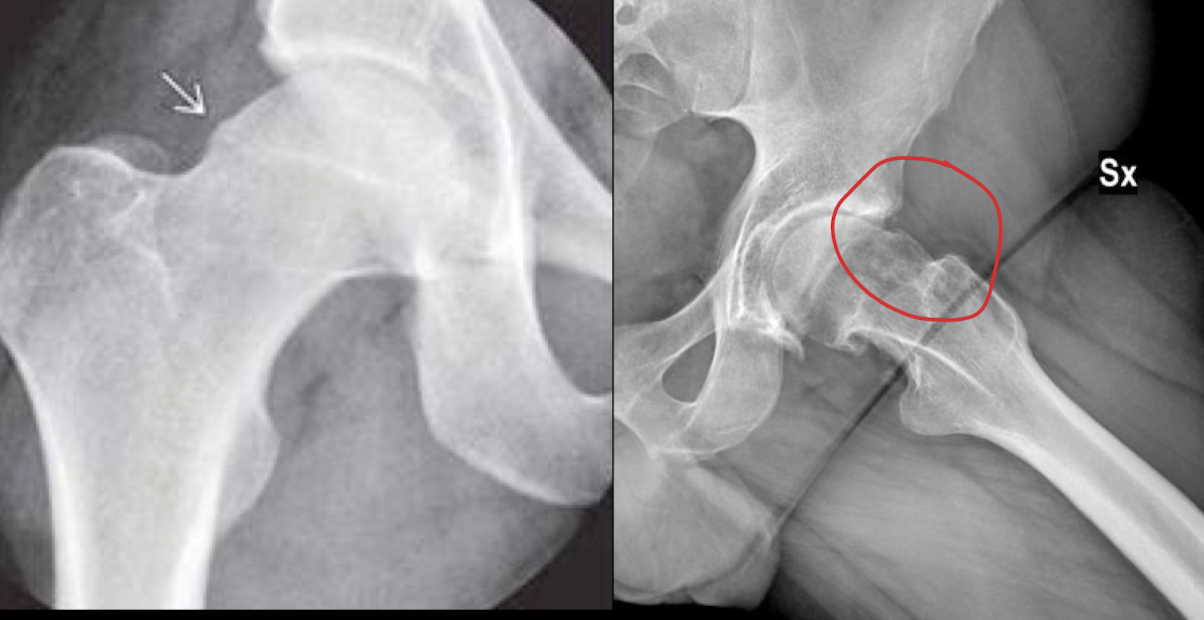

PZFAC TIPOS

A

CAM(leva): deformidad cuello femoral hombres

PINCER(pinza): sobrecobertura del acetábulo, mayor profundidad coxa profunda **mujeres

**

Mixto: CAM + PINCER

RX PZFAC

Ap y oblicua

Axial (Dunn)